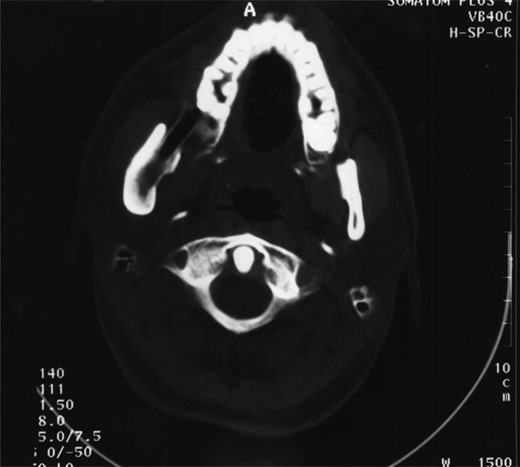

Plain films along with CT scan, with 3 mm slices, were performed a further year later and showed good bone regeneration in the right ramus and condylar neck (Figs 4 and 5). No evidence of cystic recurrence was seen and no abnormalities within the adjacent soft tissues. High-resolution magnetic resonance imaging also confirmed the absence of cystic remnants. The patient has now been reviewed for 5 years and there is no evidence of recurrence.